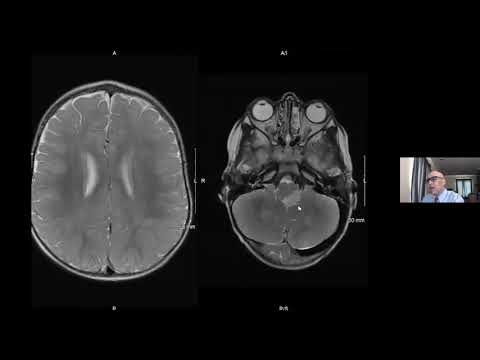

Neurocutaneous Syndromes - Developing Brainstem Lesion - Subtle Optic Glioma